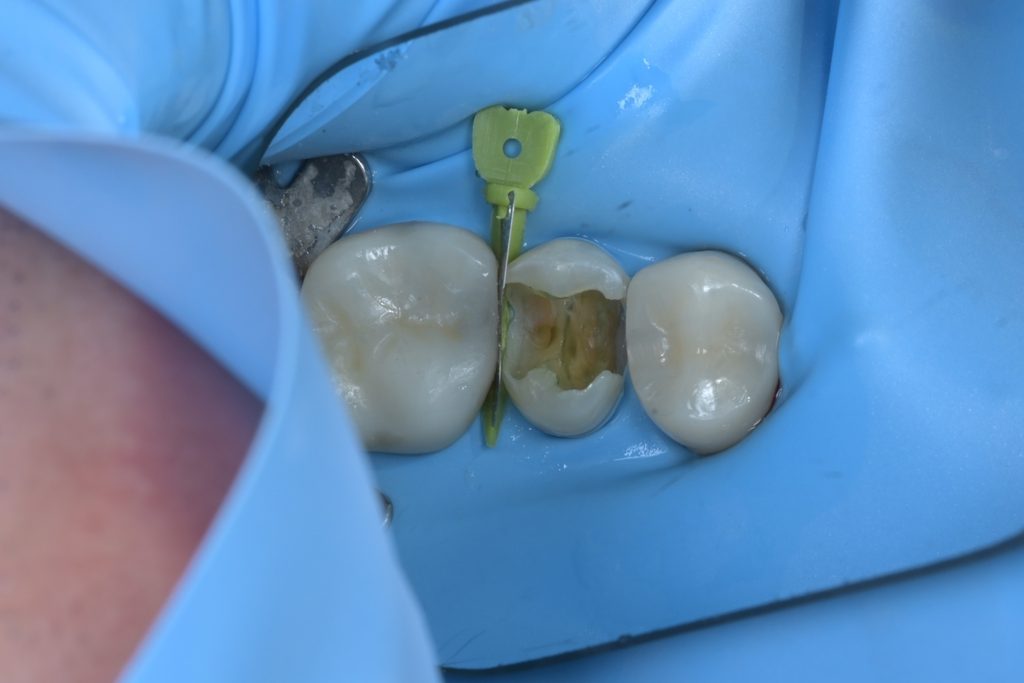

Step 2: 우식 제거

미세현미경을 사용하여 기존 수복물과 우식 조직을 세밀하게 제거합니다. 우식검사액(Sable Seek)을 사용하여 남아있는 우식 조직을 염색하고, 건강한 치질만 남을 때까지 정밀하게 제거합니다.

Step 3: 치수 노출 확인 및 평가

우식을 완전히 제거하는 과정에서 치수가 노출되었습니다. 이 시점에서 치수의 생활력과 건강도를 평가하는 것이 중요합니다.

출혈이 선홍색이고 지혈이 가능한 상태였으며, 환자분도 자발통이 없었기에 생활치수치료(VPT)를 진행하기로 결정했습니다.